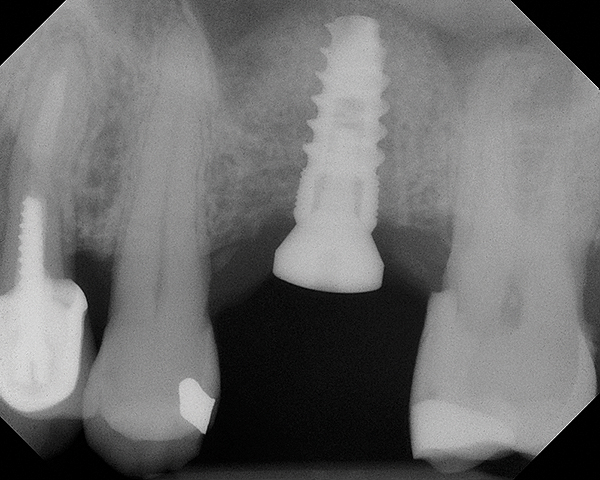

Fig 5. Radiograph of implant No. 14 and graft in place, day of placement.

Figure 5

Fig 4. Radiograph showing the sinus membrane being elevated about 8 mm supported by a composite bone graft that is partially radiolucent in the No. 14 position.

Figure 4

Fig 6. 5-month postoperative radiograph showing good healing of the augmented bone with the old floor of the sinus indistinguishable.

Figure 6

Because the bone grafting materials used in this technique need physical stability during healing to support the raised membrane, there is a high probability that significant shrinkage of the graft will occur as it heals and matures if only non-demineralized material is used. For these reasons, a composite graft using calcium sulfate, DFDBA, and mineralized particulate bone is used. A 50:50 mixture by volume of mineralized bone grafting material and DFDBA is used, to which approximately 40% calcium sulfate by volume is added. A higher percentage of calcium sulfate is used relative to that described for composite grafting in other uses, because some of the calcium sulfate will wash out during bone packing. Another advantage to this composite graft is that it is not as radiopaque as a purely mineralized graft. This allows radiographic monitoring of the bone healing around the implant, which can be used to time abutment placement on the implant. This is demonstrated in Figure 4 and Figure 5, which are radiographs taken on the day of the initial surgery showing the radiographic appearance of the composite graft, implant, and graft, and in Figure 6, a 5-month postoperative radiograph with the abutment in place. The old floor of the sinus is indistinguishable from the area of new bone. Figure 7 shows a CBCT scan (Carestream Dental, www.carestreamdental.com) taken at 4 months with the old floor of the sinus indistinguishable from the new bone formed.